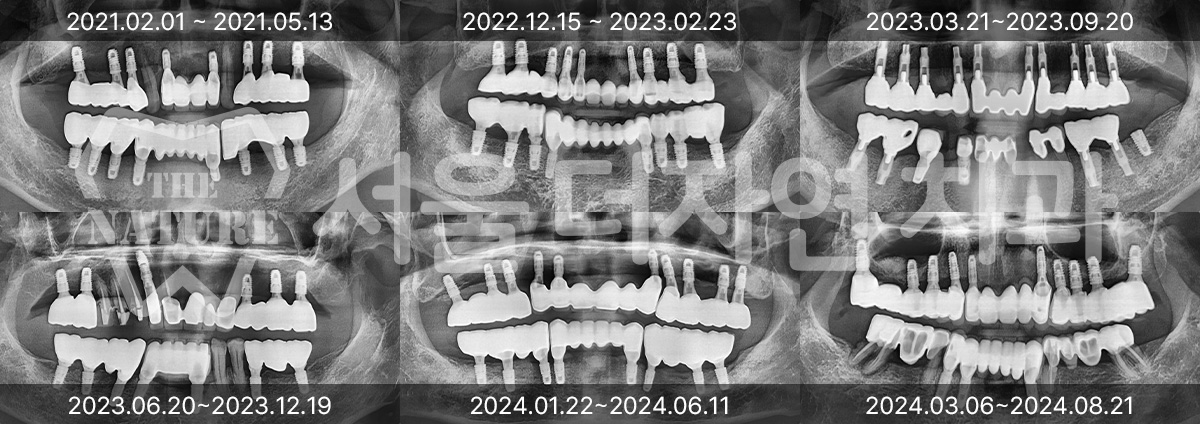

다양한 임플란트 치료 사례

#전체 임플란트

-

BEFORE: 2022.12.15

AFTER: 2023.02.23

#상악동 거상술

BEFORE: 2021.02.01

AFTER: 2021.05.13

#상악 골이식

BEFORE: 2021.11.02

AFTER: 2022.01.19

환자분들이 증명해주신

전체 임플란트 수술 전문 치과!

전체 임플란트는 치과 치료 중 난이도가 높은 편에 속합니다.

그만큼 신중한 결정이 필요한데 개인의 상태에 따른

정밀 진단이 가능한 곳이여야 하며,

식립 이후 지속적으로 사후 관리가 가능한 곳에서

꾸준한 관리가 필요합니다.

서울더자연치과는 다수의 전체 임플란트 경험으로

체계적인 계획과 식립, 사후 관리가 가능합니다.

전체 임플란트 잘하는 치과라는 소개 덕분에

지금도 많은 분이 찾아주고 계십니다.